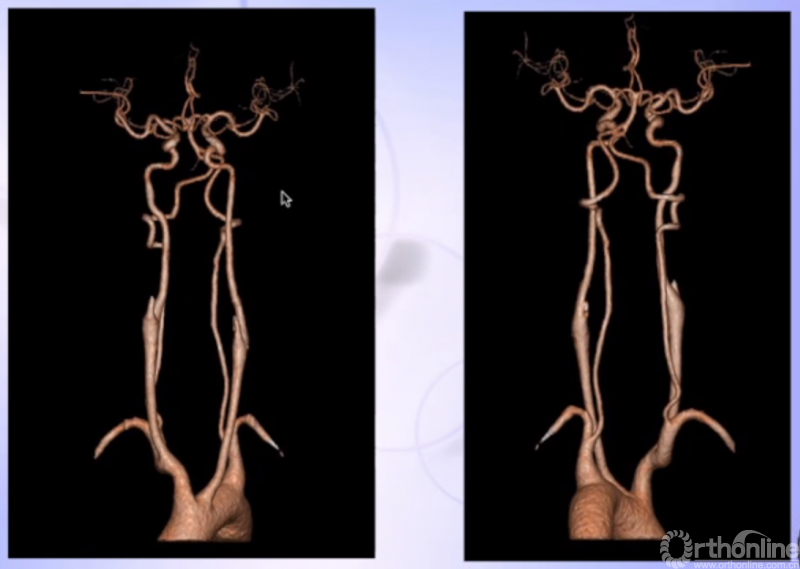

CTA